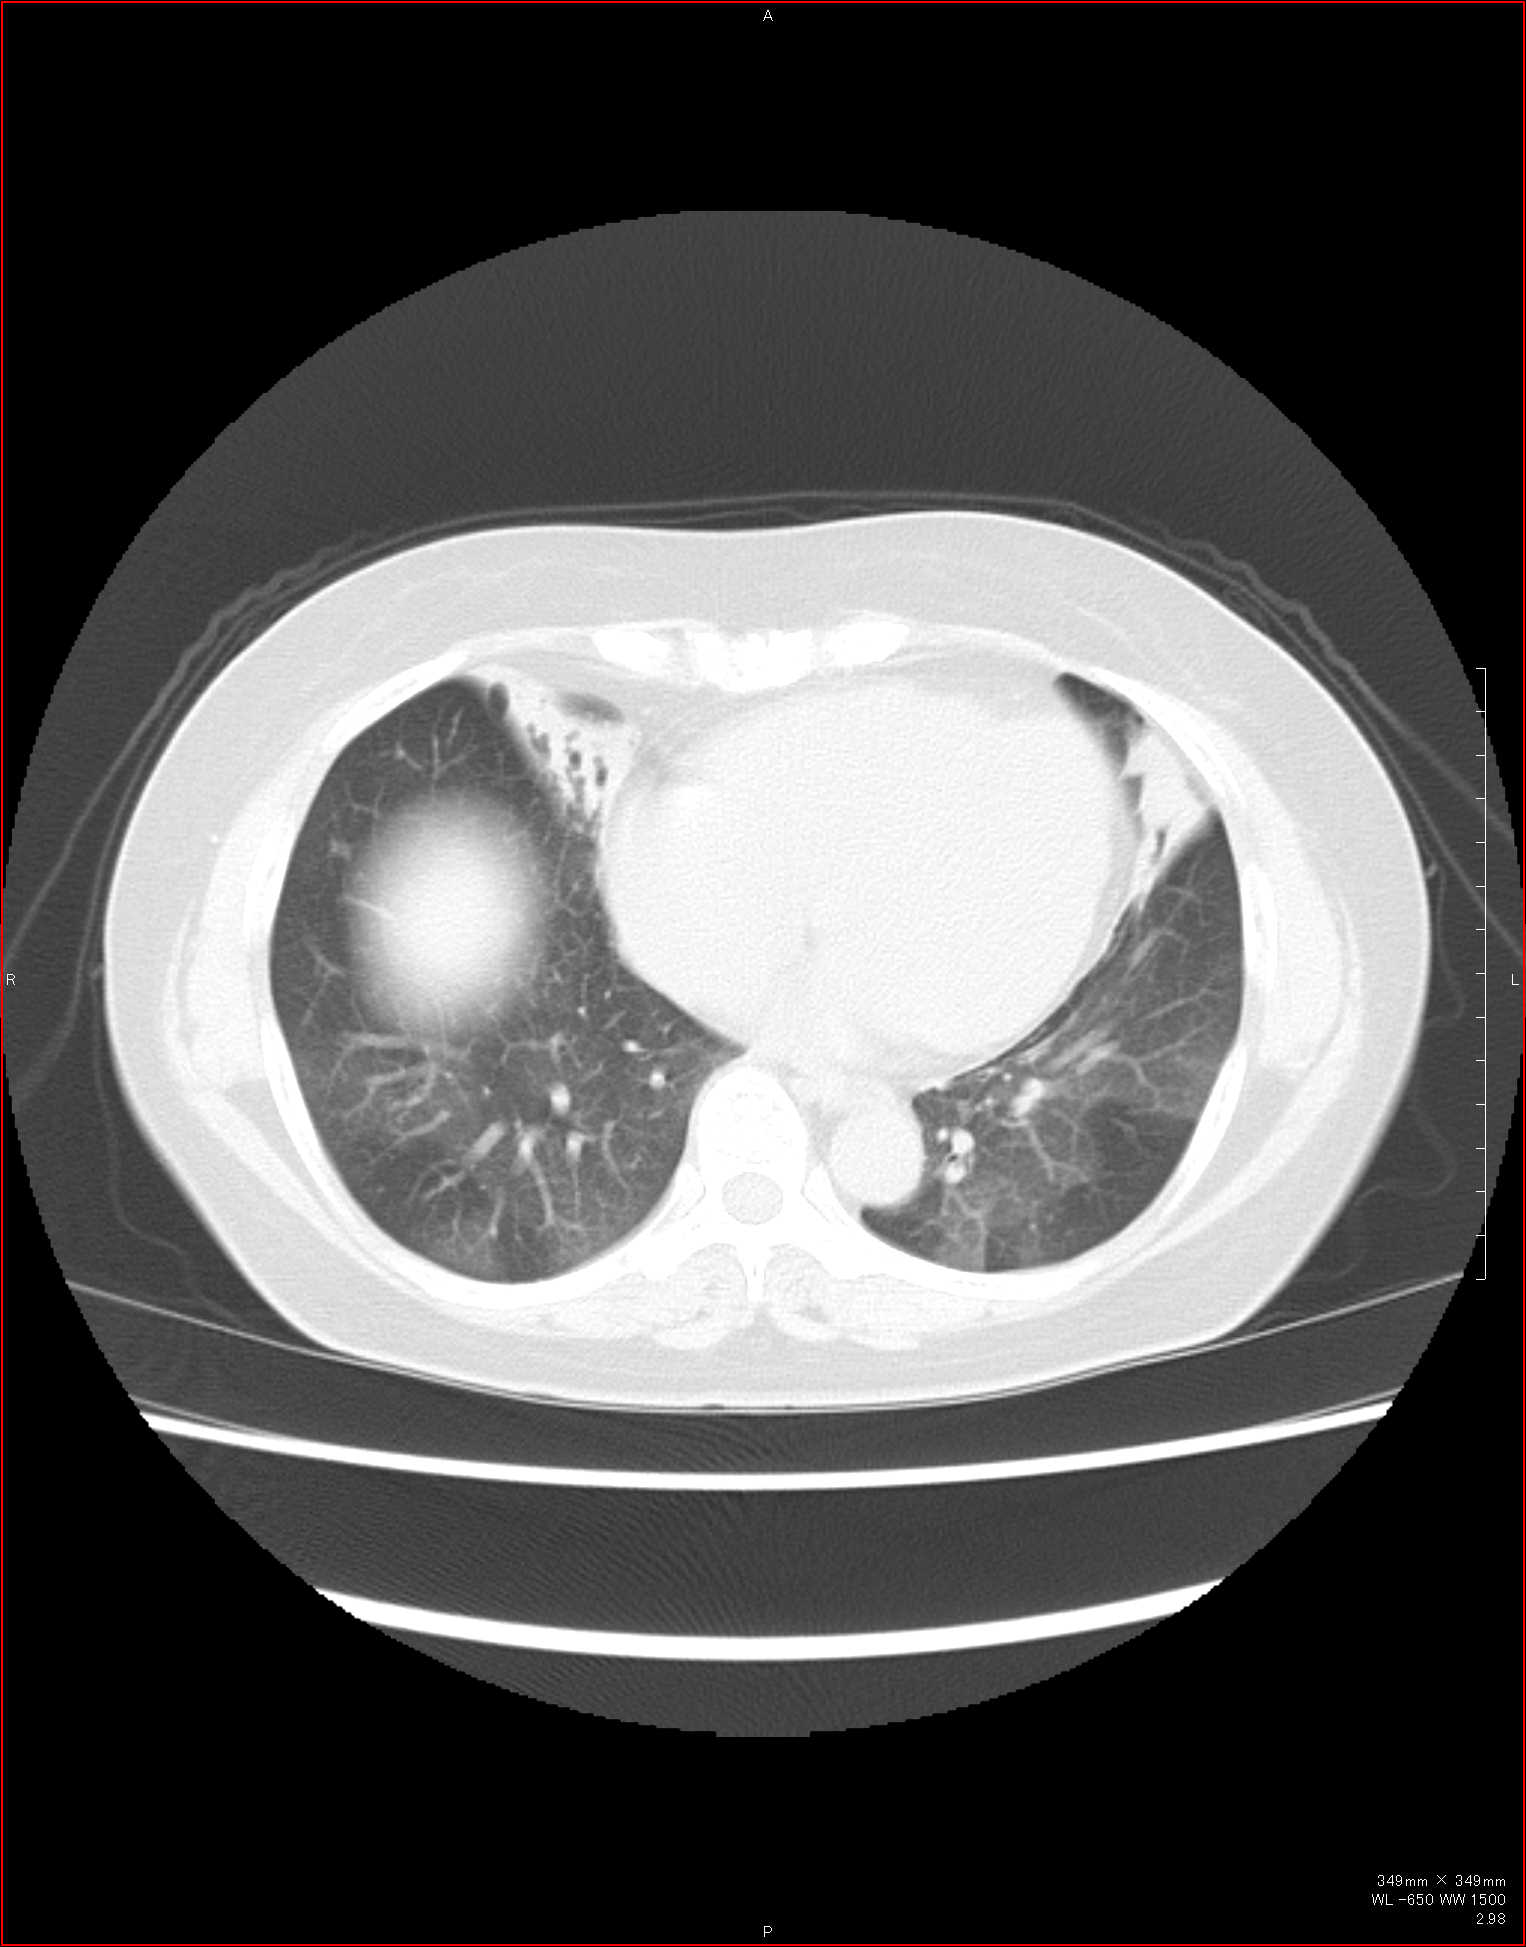

CTで見ると…

気管狭窄ですね。こういう所見もレントゲンで捉えることができるのです。